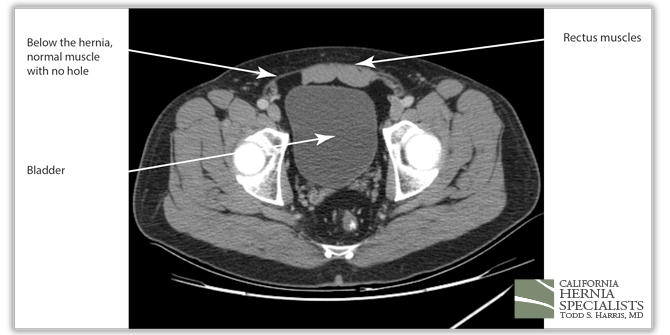

However, in this CAT scan image, there is a noticeable hole in the lower muscle wall, and the start of an inguinal hernia both on the left and the right side of the groin.

The bladder can be seen squeezing through the hole in the muscles within the patients right groin (left side of the CAT scan image). On the patients left side (right side of the image), there is only fat pushing through the hernia defect.

The 3 CAT scan images below show the patients normal muscles above the hernia, then a large hernia defect or hole in the muscle, and then the normal muscles again below the hernia defect.

The CAT scan image below compares the patient before surgery, and then after surgery when the muscle has been pulled back together and the hernia has been repaired.